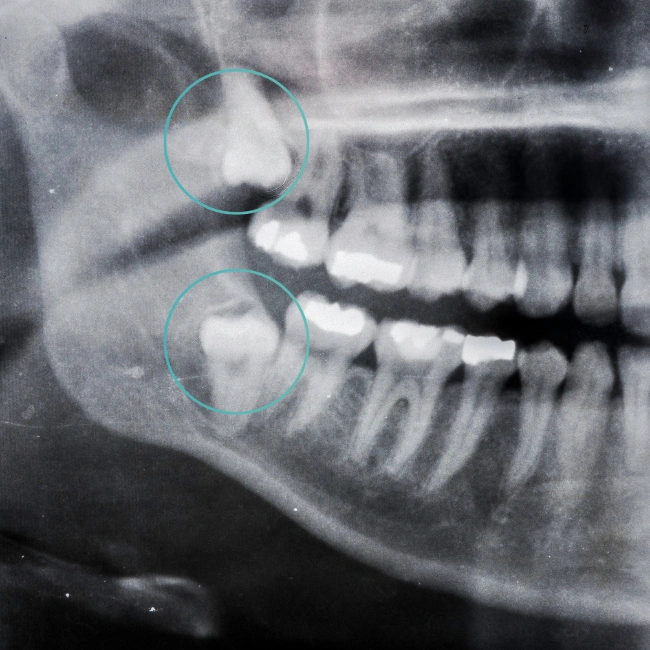

Wisdom Tooth Removal

Wisdom teeth can cause issues when there isn’t enough space for them to develop properly. They may partially emerge, grow at an angle, or become impacted, potentially leading to discomfort, swelling, or infection. Even if you aren’t experiencing symptoms, it’s important to have your wisdom teeth assessed so your dentist can check their positioning and overall health.

At Revive Dental Applecross, our experienced dentists, Dr David Norcross and Dr David O’Dowling, manage the full spectrum of wisdom tooth care — from straightforward cases to more complex situations. For complex removals or complications, we also welcome referrals from your regular dentist, ensuring continuity of care and expert management. Sedation options are available for a comfortable and stress-free experience.